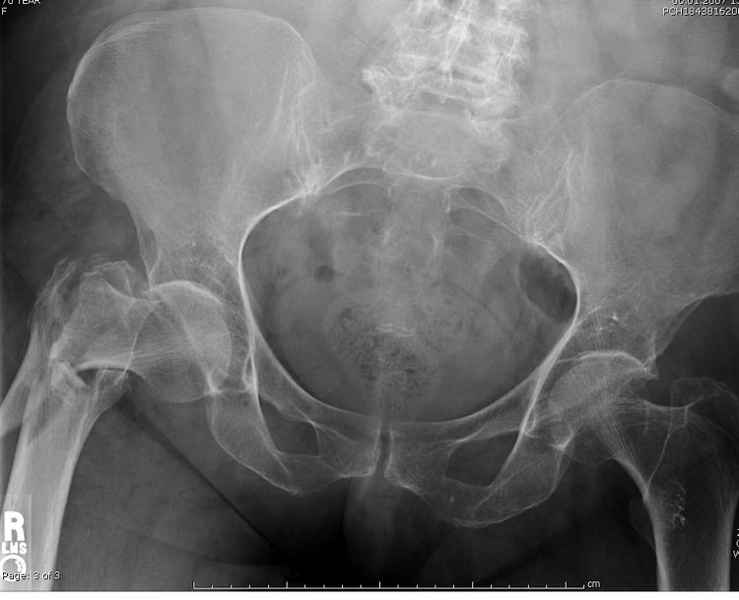

Здесь пара случаев фиксации похожих переломов:

первый высокоэнергетическая травма 36 лет

Здесь 83 года, травма в результате падения